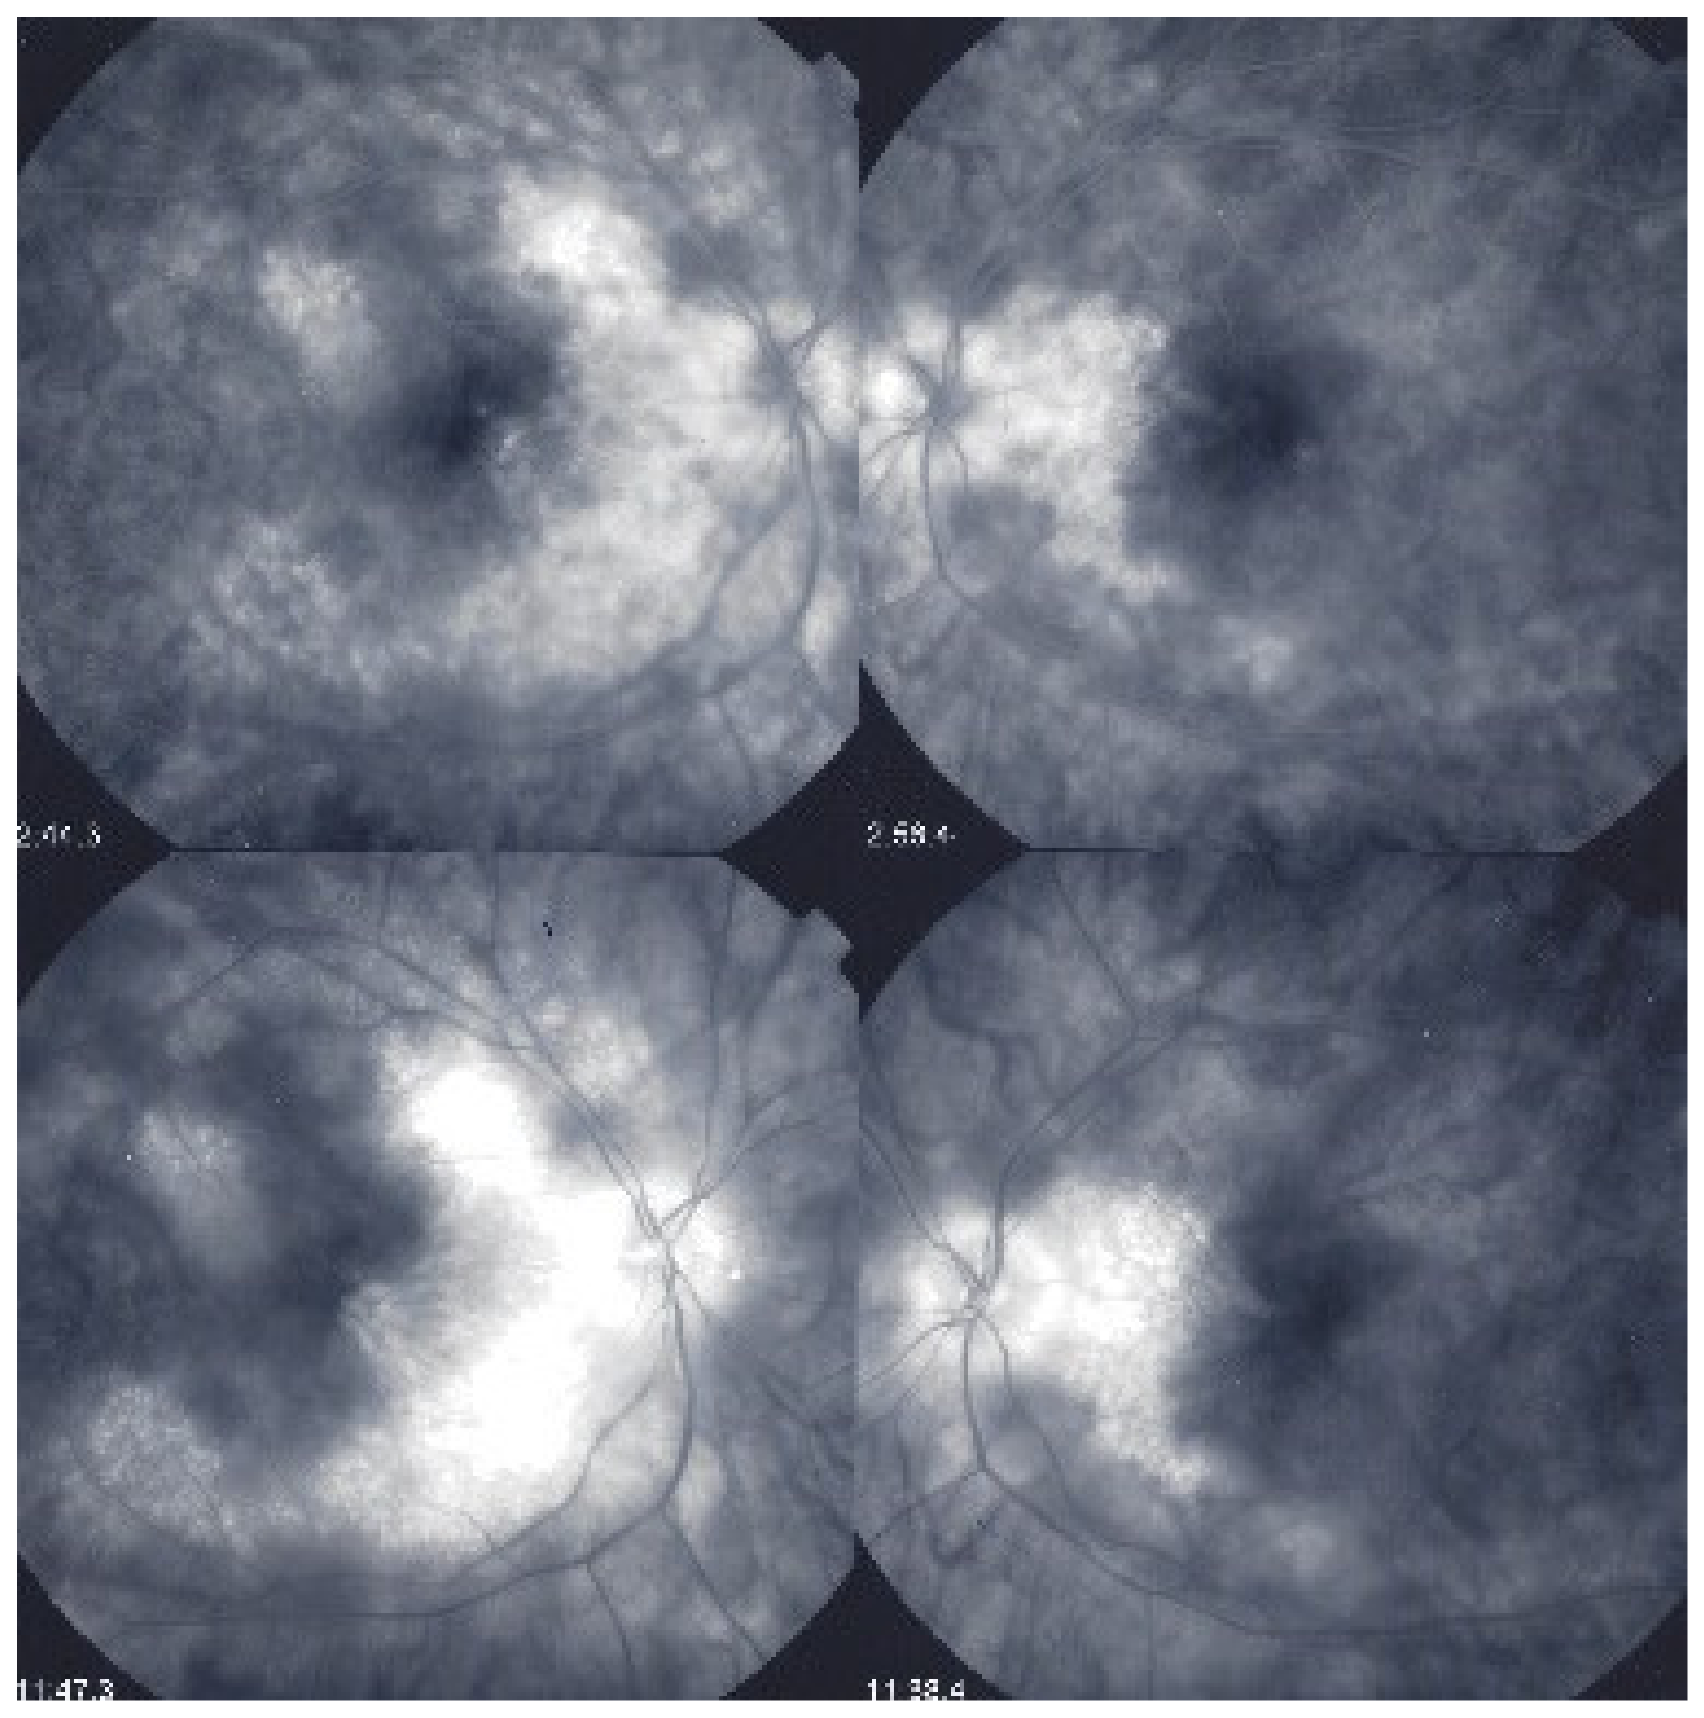

Multimodal imaging allowed precise appraisal of BRC and allowed to understand the disease mechanisms. Fundus photography is marginally useful to follow BRC evolution as they indicate stromal scars while ICGA is the most sensitive modality to document disease activity (Figure 41). When treated early, based on ICGA findings, fundus birdshot lesions may never appear. As far as FA is concerned, during the early exudative stage of BRC, three characteristic signs are observable using FA. In the early angiographic frames, there is “an increased retinal circulation delay”, which is in fact a pseudo-delay explained by the diffuse capillary exudation of fluorescein to the extent that there is not enough dye to normally mark the large veins. In contrast, the large ICG complex does not leak from retinal capillaries and normally marks large retinal veins, which indicates that there is no real hemodynamic slowing (Figure 42). Consequently, the first specific FA sign in BRC is massive and diffuse retinal capillary leakage with diffuse retinal edema, which was already observed by Gass [106] (Figure 42).

Figure 42.

Pseudo-delay in retinal circulation. A patient in the exudative stage of BRC exhibits no fluorescein marking of large veins at 42.3 s. (a) and 47.4 s (b) after injection. This is not due to an increase of arterio-venous circulation time, but to massive extrusion of the small fluorescein molecule from retinal capillaries and larger vessels. This phenomenon is revealed by ICGA; opacification of large veins occurs normally at 24.0 s (c), as the large ICG complex does not extrude from retinal vessels.